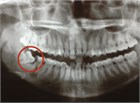

Pericoronitis is a special type of acute periodontal abscess that occurs when gingival tissue that overlies a partially erupted or impacted tooth, usually a third molar or wisdom tooth, becomes inflamed. When dental referral is not readily available surgical removal of the operculum can relieve pain.

impacted third molar

Pericoronitis